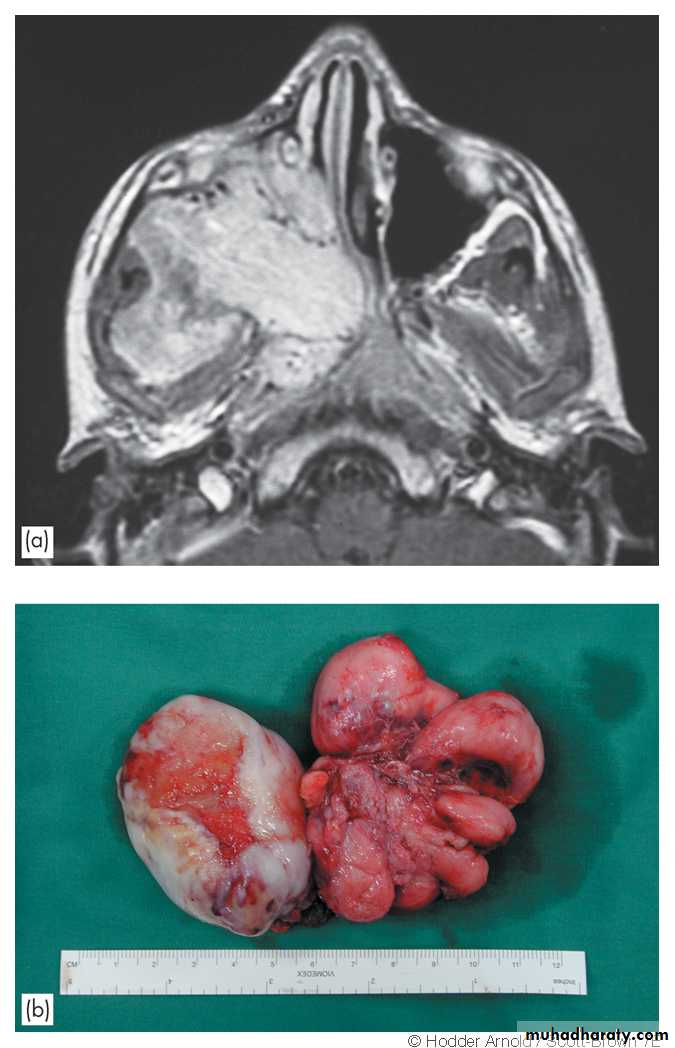

The tumor takes origin from the periosteum on the lateral wall of the nasopharynx close to the sphenopalatine foramen .

Extension occurs:

1. Anteriorly to the nasal cavity and ethmoid.

2. Superiorly to the base of the skull.

3. Laterally to the pterygoid fossa, maxillary antrum and orbit.

1. Endoscopy and posterior rhinoscopy: smooth, rubbery lobulated mass in the nasopharynx.2. Middle ear effusion.

3. Mass in the nasal cavity or on the cheek if the tumour has extended anteriorly or laterally.

4. Proptosis results from extension of the tumour to the orbit through the infraorbital fissure.

1. Surgical excision Haemorrhage is the main danger of operation, so adequate blood should be prepared before the operation.2. Embolization is indicated preoperatively to control the vascularity of the tumor.